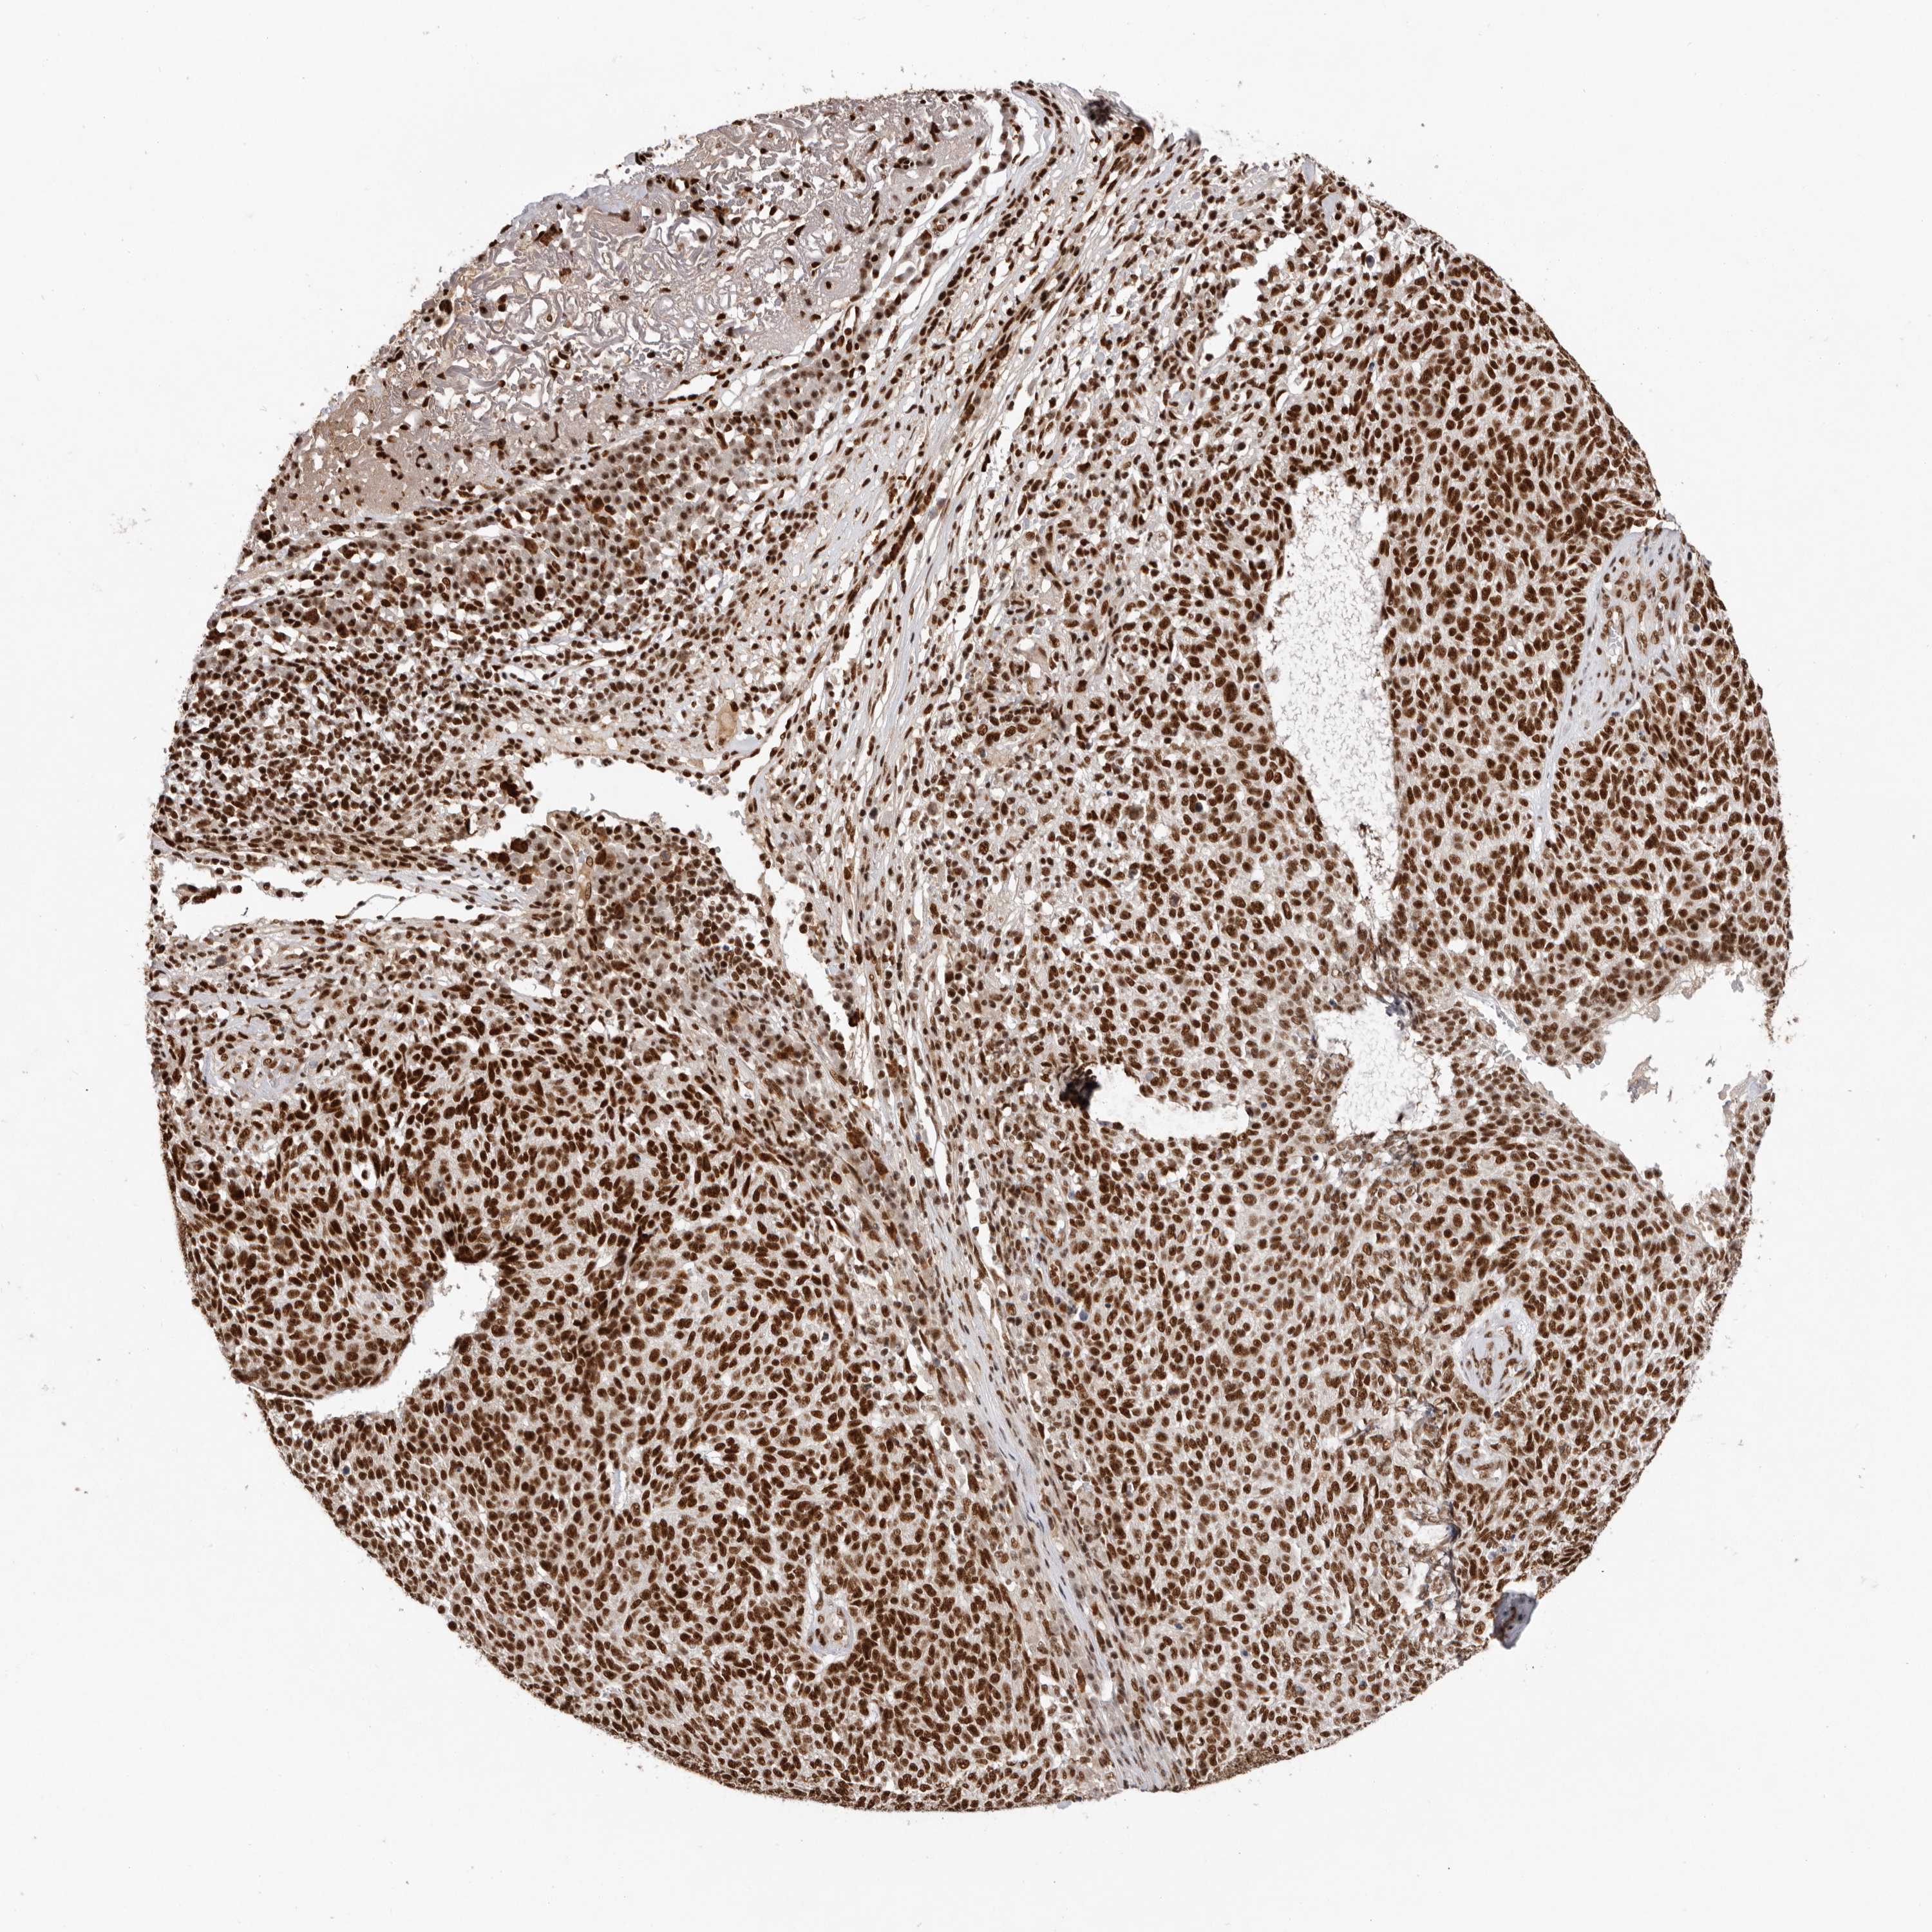

SKIN CANCER - Protein expressioni

A mouse-over function shows sample information and annotation data. Click on an image to view it in a full screen mode. Samples can be filtered based on level of antibody staining by selecting one or several of the following categories: high, medium, low and not detected. The assay and annotation is described here.

Antibody stainingi

Antibody staining in the annotated cell types in the current human tissue is reported as not detected, low, medium, or high, based on conventional immunohistochemistry profiling in selected tissues. This score is based on the combination of the staining intensity and fraction of stained cells.

Each image is clickable and will lead to virtual microscopy that enables deeper exploration of all samples and also displays staining intensity scores, fraction scores and subcellular localization as well as patient and tissue information for each sample.

Antibody HPA028647

Staining

High

Intensity

Strong

Quantity

>75%

Location

Nuclear

Basal cell carcinoma

Squamous cell carcinoma, NOS

Squamous cell carcinoma, metastatic, NOS